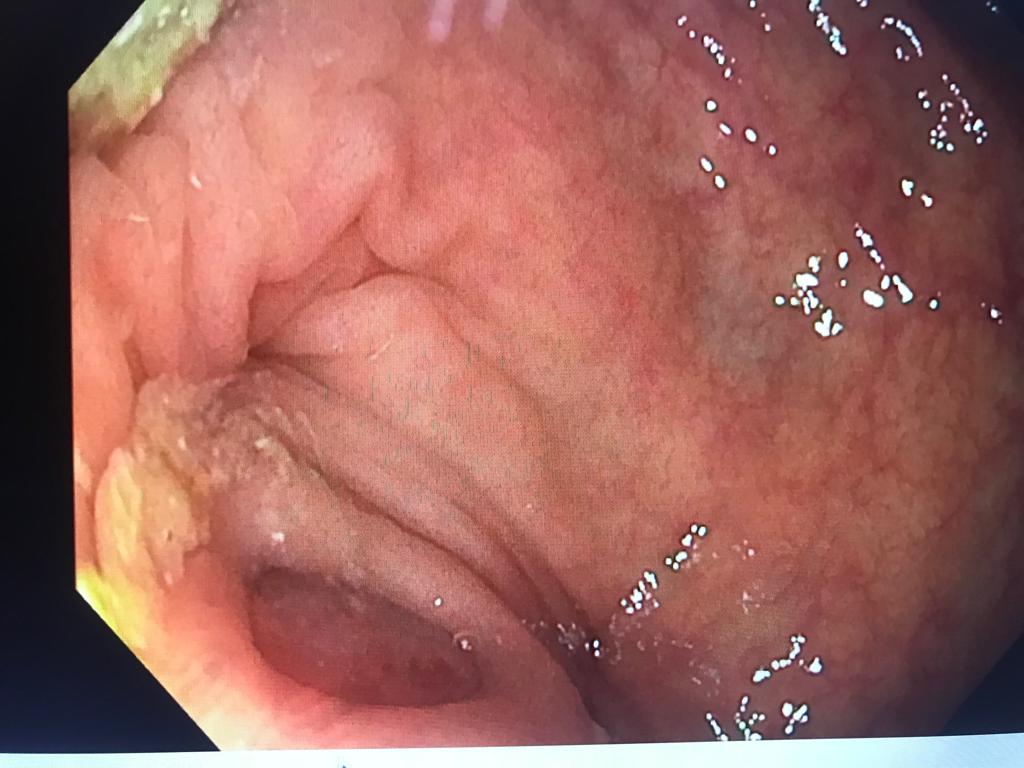

Femme 60 ans coloscopie de dépistage

Aspect bombant de l'orifice appendiculaire, évoquant la présence d'une tumeur de l'appendice

Bombement de l'orifice appendiculaire, faisant suspecter la présence d'une tumeur

Lumière blanche on devinne la présence d'un polype derrière l'orifice